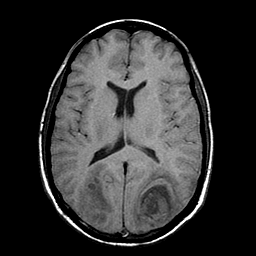

Sarcoma, MR Study #1 mr-t1 -- Slice #13

[Home][Help][Clinical] Slice 13